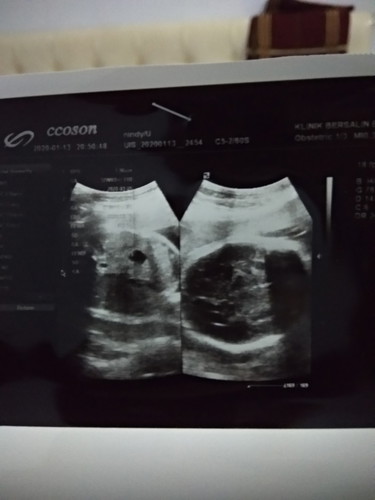

sungsang

Gimana biar janin gak sungsang bun. Usia kehamilan 31 week .